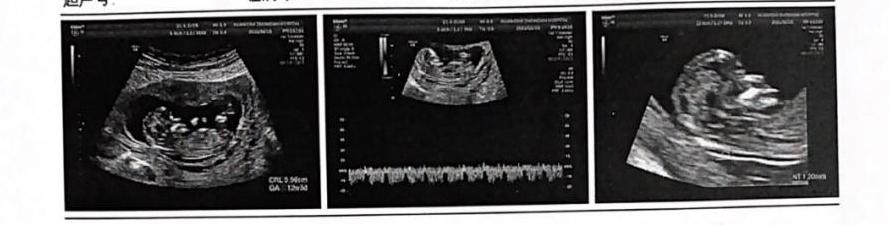

孕妇为经产妇,以上数据尚可,如无意外可顺产,但孕妇强调了流产意向,且根据前次产检超声孕周12W+3d,推算目前孕周为13周,可以流产,遂诊断为早期人工流产,孕13周。